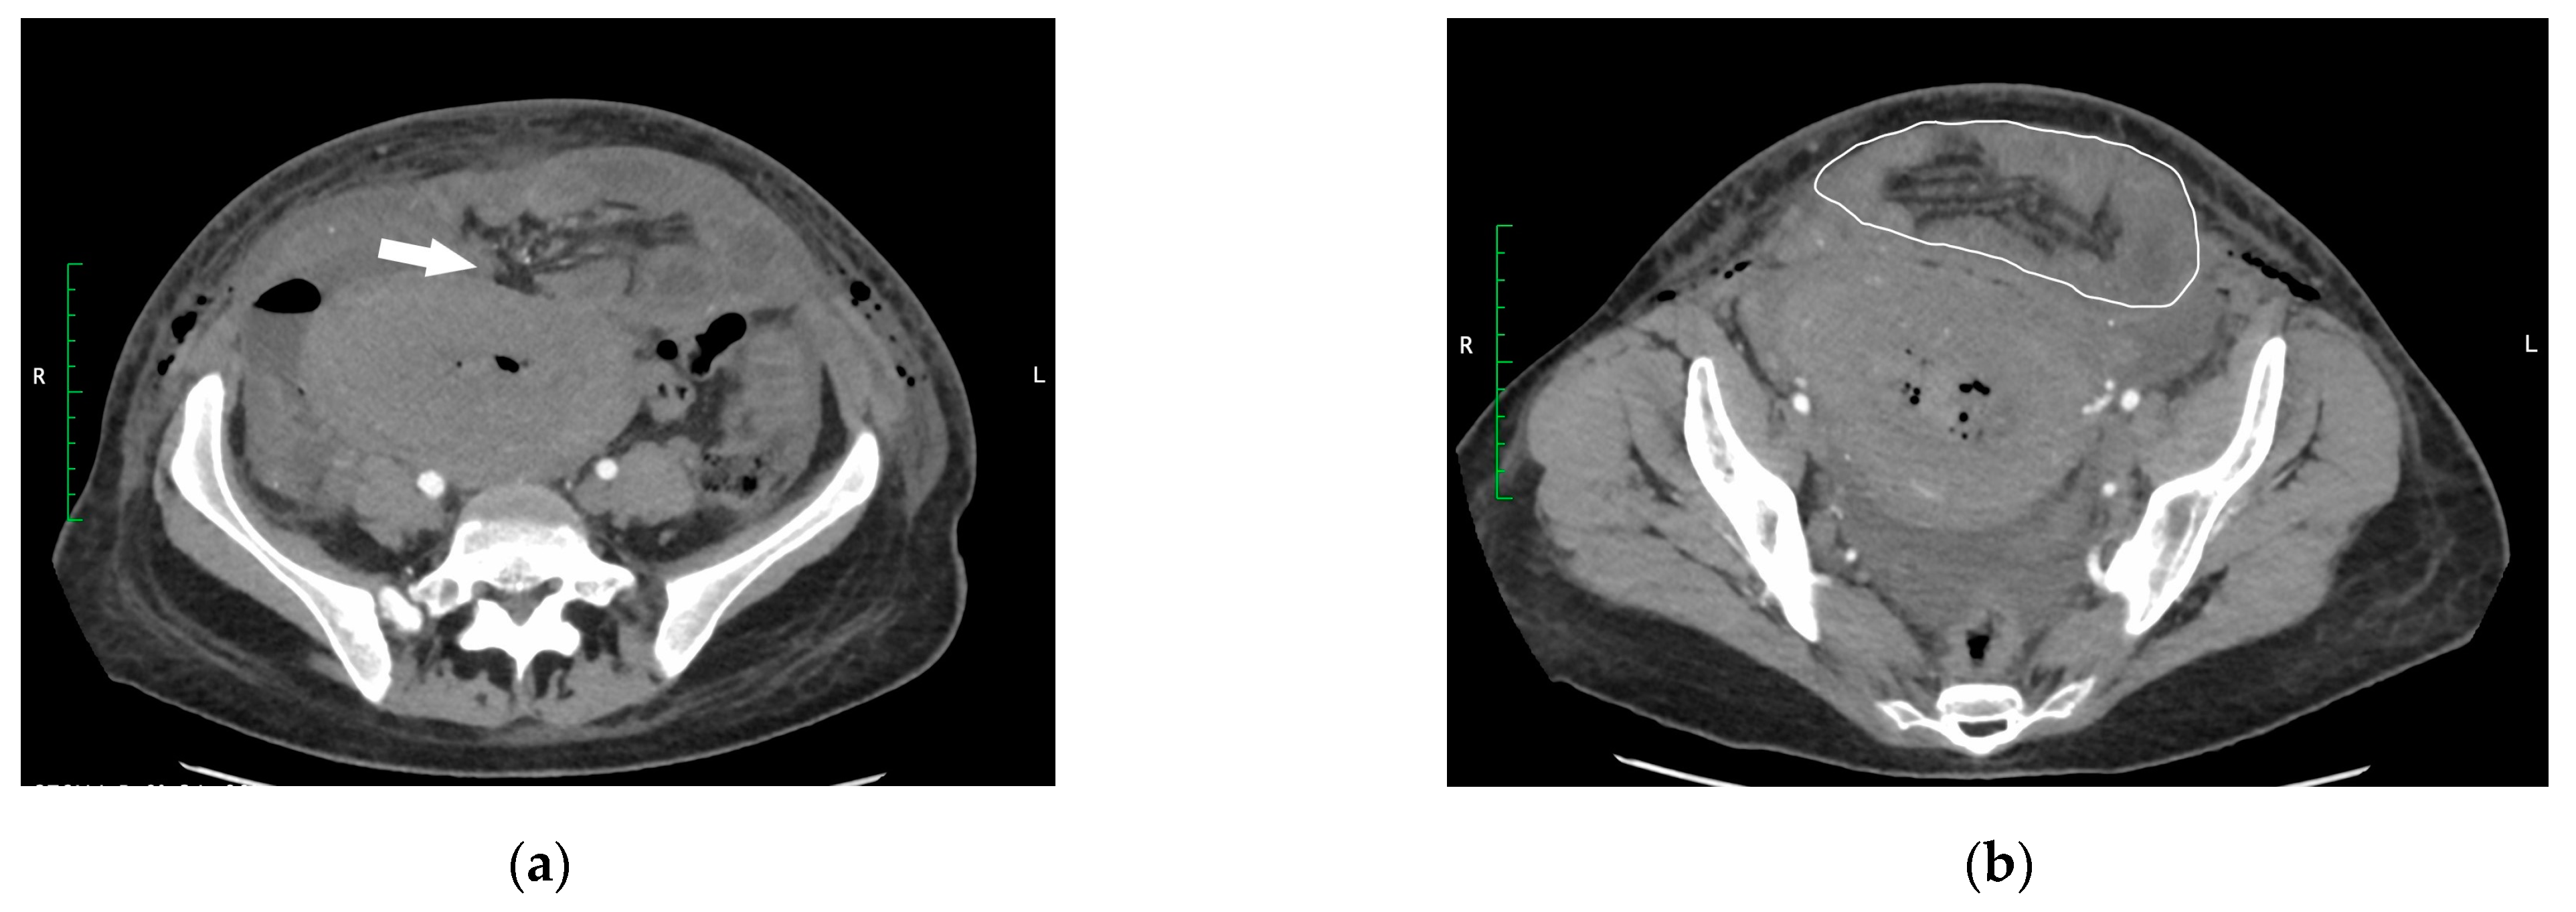

The first postoperative day was uneventful. On the second postoperative day, the patient complained about pain in the epigastrium. The abdominal ultrasound scan revealed the free fluid and mild oedema of intestinal walls. Urinary tract injury was suspected since the patient initially showed no signs of bowel obstruction—was tolerating oral intake, passing gas and had bowel movement. A diagnostic ultrasound-guided laparocentesis was performed to confirm the diagnosis. Serohemorrhagic fluid was sent for the creatinine test and culture. The creatinine test and culture were negative, and urinary tract injury was ruled out. On the third postoperative day, the patient complained about diffuse spastic abdominal pain and vomiting. During the examination, the abdomen was diffusely painful with marked tenderness in the epigastrium. Peritoneal signs were negative. The auscultation revealed that hyperactive bowel sounds were present. Abdominal radiography showed signs of small-bowel obstruction. The abdominal-computed tomography (CT) scan revealed an infraumbilical abdominal wall defect approximately 2.5 cm in diameter (Figure 1a) with an eventration containing distal loops of ileum, occupying an area of 12.3 × 6.9 cm (Figure 1b).

Figure 1. (a) CT scan showing an infraumbilical abdominal wall defect (white arrow). (b) Eventration of the small bowel (white outline).